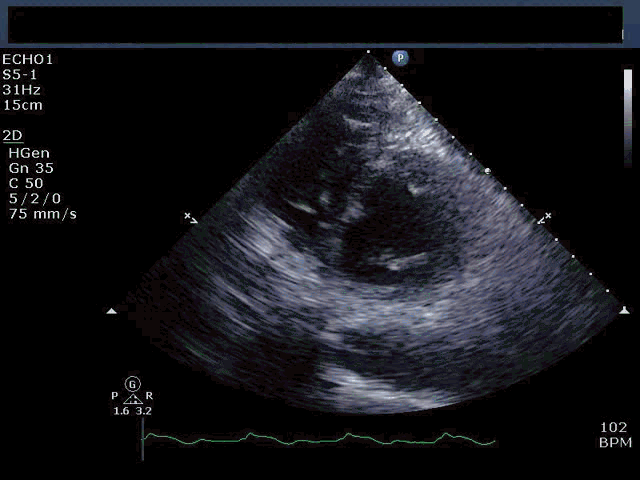

入院时,血压92/40 mm Hg,心率122bpm,律齐,呼吸急促,心电图诊断为下壁STEMI。体格检查:四肢厥冷潮湿。胸骨左下缘听诊高亢的3/6级收缩期杂音并向腋中线传导。经胸超声心动图示二尖瓣结构正常,无明显的二尖瓣反流。下间隔和下壁基底段无运动,远段间隔和前侧壁代偿性运动增强(视频1)。

视频1